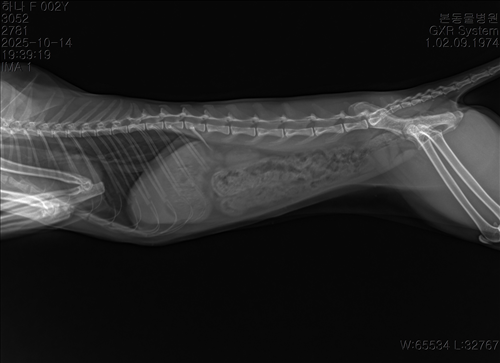

10.10/10.12/10.14일 엑스레이입니다

10월 10일 포도를 토해논후로 식욕저하 기력저하가 있어서 동물병원에 방문해서 엑스레이를 찍었는데 우선 지켜보자는 말과 소화제처방과 주사를 맞고 집왔습니다 그 후로도 안먹어서 12일에 동물병원에가서 혈액검사도 하고 수액도 맞았습니다 췌장쪽 수치가 좀 높아서 췌장쪽만 다시 검사했는데 수치는 괜찮았습니다 식욕촉진이랑 소화제처방 받아서 먹이는데 식욕저하도 여전하고 기력이 좀 없고 10일부터 14일까지 대변을 못보고있어서 14일에 병원에 가서 엑스레이랑 초음파를 했는데 장폐색일수도 있다는 말을 들었습니다 초음파상으로는 소장쪽 이물이 의심된다고 하셨어요ㅠ